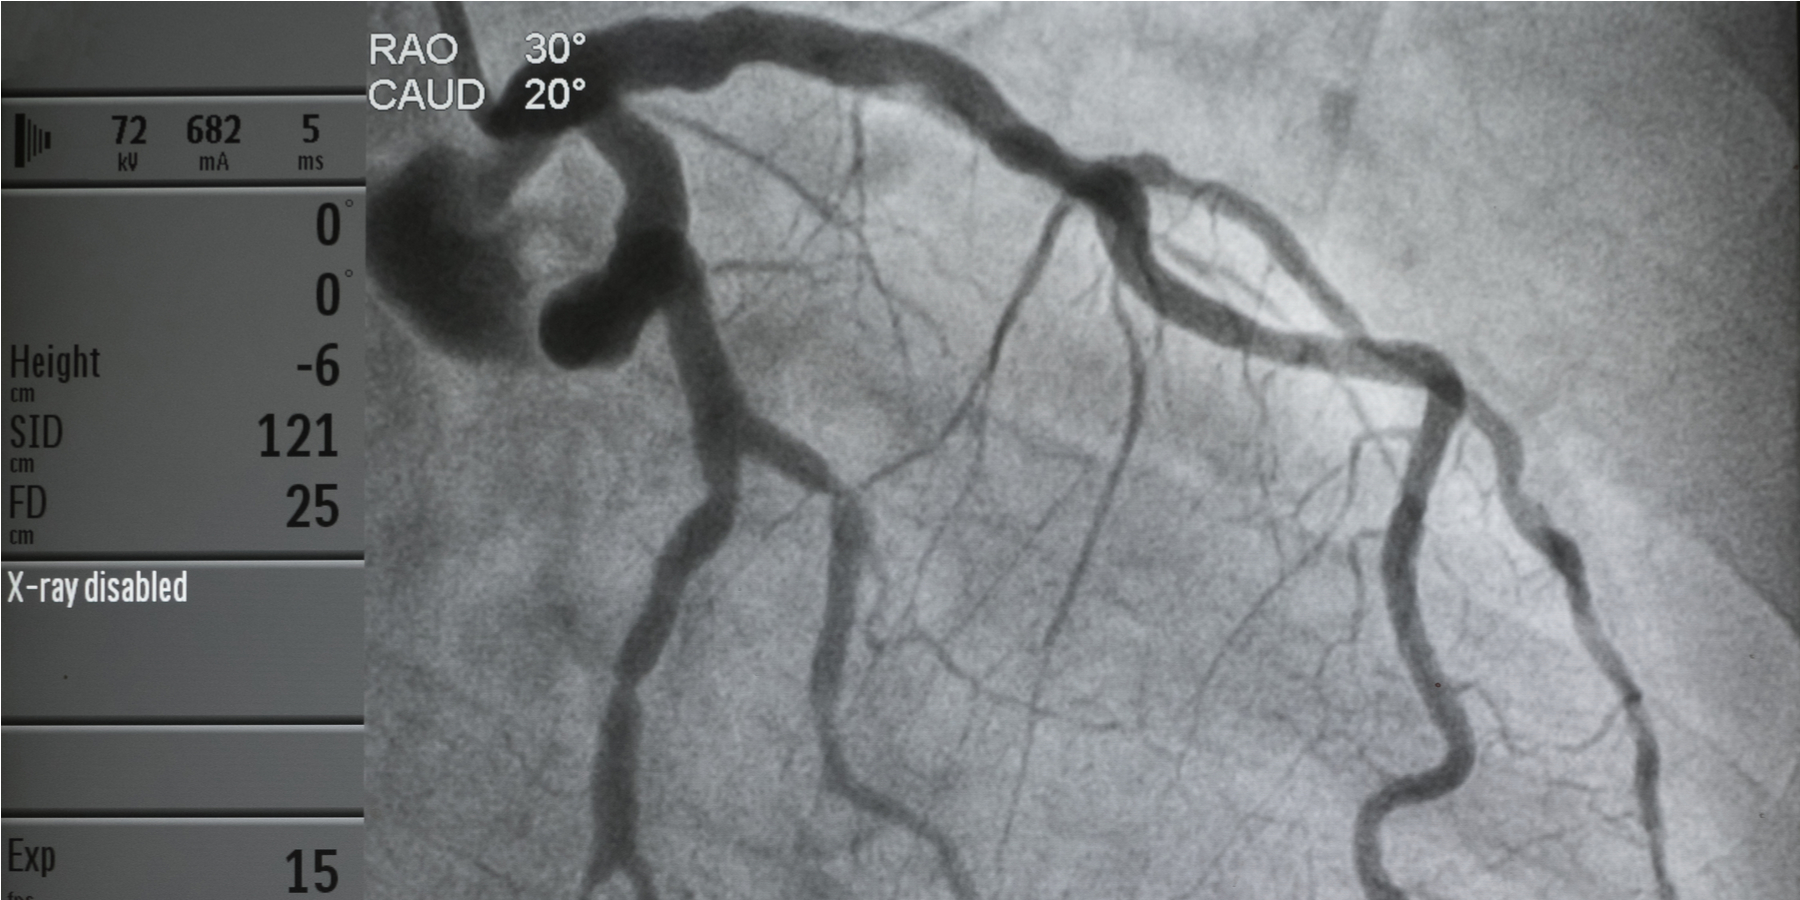

Cardiac catheterization image showing multiple luminal irregularities Heart Catheterization Journal Article the 2016 society for cardiovascular angiography and interventions expert consensus statement. the aim of this review is to highlight common preprocedure, intraprocedure, and postprocedure. the aim of this review is to highlight common preprocedure, intraprocedure, and postprocedure. in this article, we will summarize the anatomy, physiology, and indications of left heart catheterization. the procedure can. Heart Catheterization Journal Article.